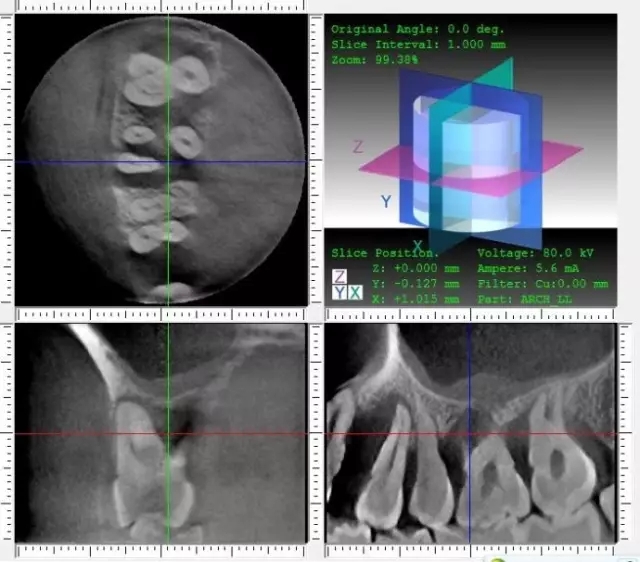

右上區(qū)的CT截圖顯示:14近中牙槽骨吸收已經(jīng)到達(dá)根尖下方;

16牙槽骨破壞已經(jīng)接近上頜竇,而且已經(jīng)有了上頜竇粘膜增厚的現(xiàn)象,此區(qū)段在做手術(shù)的時候要注意與上頜竇穿通的問題;根面顯示有大片齦下牙石。